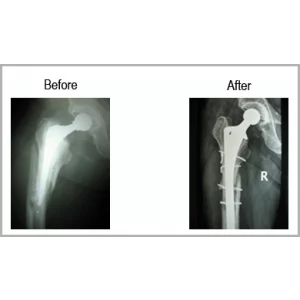

Details of Total Hip Implant In Place With Fracture Femur

Total Hip Implant In Place With Fracture Femur

A Male Aged 63 Years Was Operated For Right Total Hip Replacement. He Met With An Accident. He Fractured His Thigh Bone-femur With Total Hip Implant In Place.He Underwent Revision Of Femoral Component With Special Implant With Wiring Of The Fracture. Now He Is Walking Normally Without Any Type Of Discomfort.... Read more